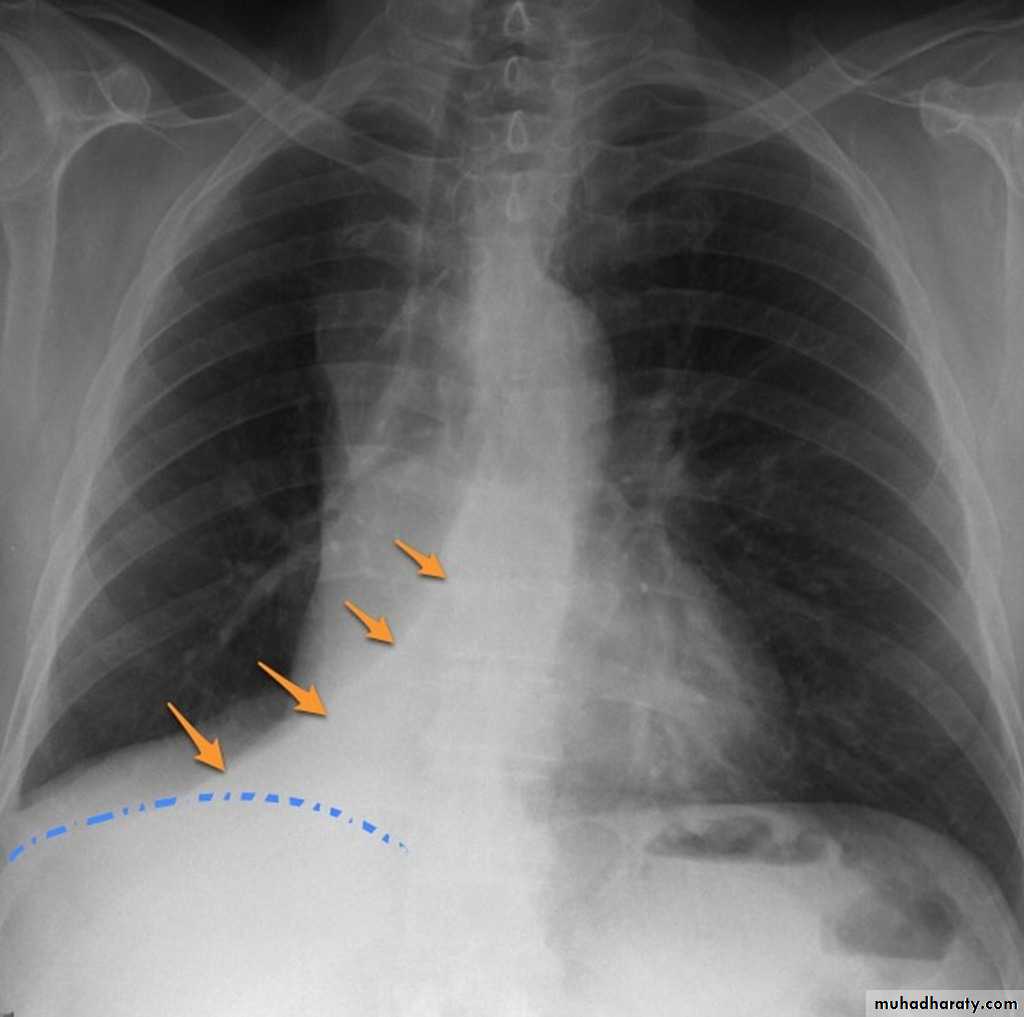

Pleural effusionPleural effusion tends to be used as a catch-all term denoting a collection of fluid within the pleural space. This can be further divided into exudates and transudates depending on the biochemical analysis of aspirated pleural fluid. Essentially it represents any pathological process which overwhelms the pleura's ability to reabsorb fluid.

Radiographic appearances

Plain radiographChest radiographs are the most commonly used examination to assess for presence of a pleural effusion, however it should be noted that on a routine erect chest x-ray as much as 250-600 ml of fluid is required before it becomes evident 6. A lateral decubitus film is most sensitive, able to identify even a small amount of fluid. At the other extreme, supine films can mask large quantities of fluid.

CXR (erect)

Both PA and AP erect films are insensitive to small amounts of fluid. Features include:

blunting of the costophrenic angle

blunting of the cardiophrenic angle

fluid within the horizontal or oblique fissures

eventually a meniscus will be seen, on frontal films seen laterally and gently sloping medially (note:

A subpulmonic effusion (infrapulmonary effusion) may be seen when there is previously established pulmonary disease, but can also be encountered in normal lungs , They are more common on the right, and usually unilateral

with large volume effusions, mediastinal shift occurs away from the effusion (note: if coexistent collapse dominates then mediastinal shift may occur towards the effusion)